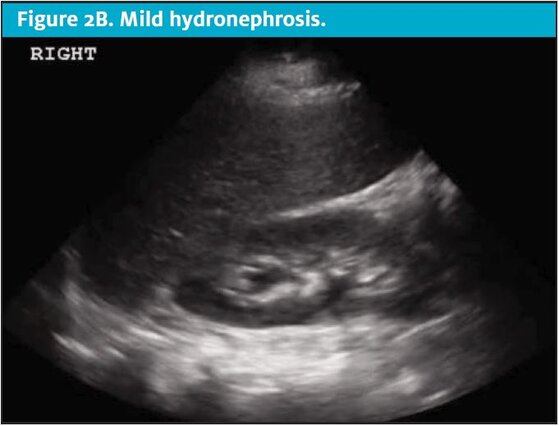

A Pocus Based Approach To Acute Renal Colic In The Urgent Care Center Journal Of Urgent Care Medicine